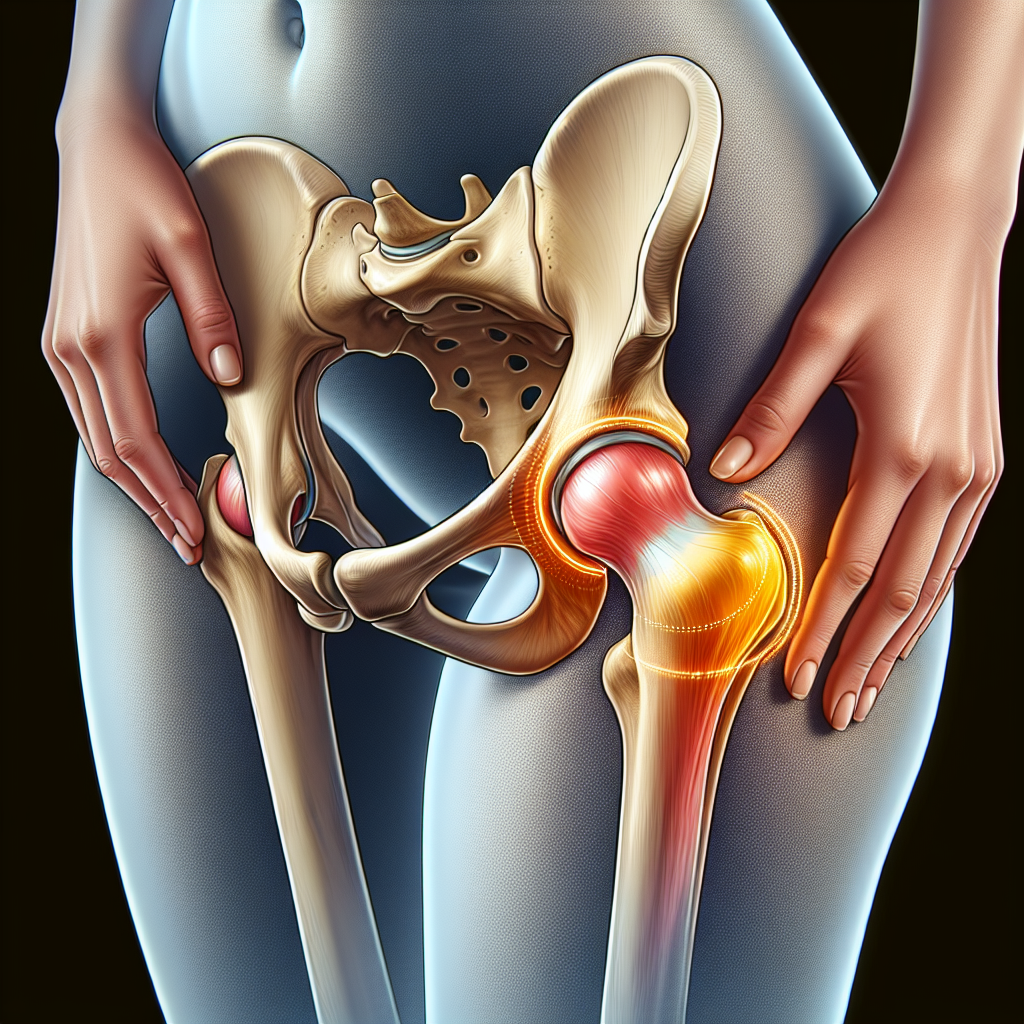

Hip bursitis vs hip labral tears: what’s happening in the hip?

Bursitis basics

Hip bursitis refers to inflammation of a small fluid-filled sac, called a bursa, that cushions the bones and soft tissues around the hip. Repetitive movements, overuse, or prolonged pressure on the outer hip can irritate this bursa, leading to a localized ache over the outer thigh bone area. You might notice tenderness to touch near the bump at the top of the thigh, and the pain can be aggravated by lying on the affected side or climbing stairs. For many people, rest and gentle, targeted movement help over time, but addressing underlying factors is important.

Labral tear basics

A hip labral tear involves the cartilage ring (the labrum) that deepens the hip socket. Tears can cause deep or groin-related hip pain and may be accompanied by a catching, locking, or giving-way sensation during movement. They often arise from a twist or pivot, prior hip joint issues, or structural factors in the joint. Not all labral tears cause noticeable symptoms, and many people benefit from conservative care first. Still, a tear can influence how the joint moves and how it feels during activities like bending, twisting, or crossing your legs.

Pain location and quality

Bursitis pain most often concentrates on the outer hip, near the greater trochanter, and may feel sharp with activity or a dull, persistent ache with rest. Labral tear pain often centers deeper in the hip or groin and may radiate to the buttock; some people describe a dull ache that worsens with hip rotation or certain positions. Tenderness to palpation over the hip bursa is common with bursitis, while labral tears may be more related to joint movement and timing rather than constant tenderness.